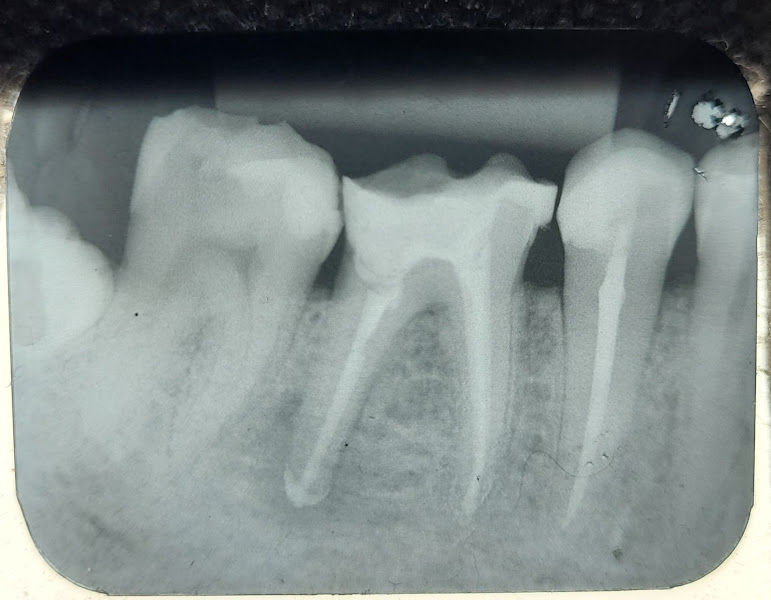

Tratei alguns canais com o Dr Ricardo, e o atendimento foi ótimo durante todo o processo. Desde a investigação da dor, a descoberta do problema, o tratamento e o pós. Uma das coisas que mais notei e senti como diferencial, foi o quanto ele sinalizava e detalhava cada intervenção. Isso me deixou bem mais tranquila e confiante. O fato de ele compartilhar o raciocínio e me incluir nas discussões me deu a tranquilidade de estar ciente de cada etapa do meu próprio tratamento. Além disso, a disponibilidade e o cuidado no pós operatório foram sempre impecáveis, garantindo que o processo todo ocorresse com mais segurança. Recomendo!